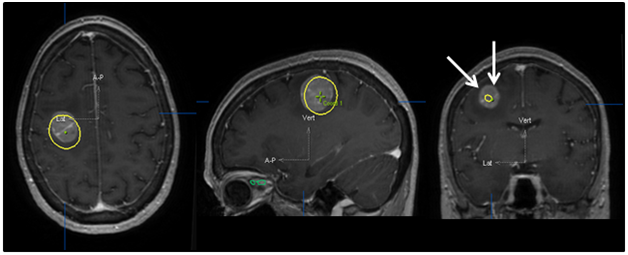

SRS is image-based treatment. All salient anatomic features of the SRS patient, both normal and abnormal, are commonly defined with CT and/or MRI. Both high three dimensional spatial accuracy and tissue-contrast definition are critical to the optimal definition of target(s) and critical structures for SRS. Imaging, whether CT or MRI, is crucial for localizing target boundaries as well as generating target coordinates for accurate treatment beam localization. Precise SRS treatment planning and delivery requires as a prerequisite that the target position is unchanged between image acquisition and treatment planning and delivery. In general, an intracranial target is not considered a moving target. Therefore, with rigid image registration and fusion, the MRI defined target and normal structures should accurately represent their relative physical position in space. Re-imaging of the brain is often done to evaluate for possible tumor progression, however, target migration between the time of imaging and treatment planning and delivery is typically not a concern. The present case illustrates a potential pitfall in the commonly made assumption that the location of the intra-cranial target is fixed in relation to the cranium and surrounding structures. In this study, the tumor position shifted within 12days, as shown in Figures 2 & 4. This resulted in a significant GTV mismatch of 3.312cc (28.3%) and a shift of the isocenter by 3.4 mm posteriorly, 0.3mm laterally and 2.5mm inferiorly (Figure 4). As demonstrated in Figure 5, if the pre-steroid MRI had been used for target delineation and planning, a significant portion of the GTV would not have been covered by the prescription dose (90% isodose line). The DVH confirmed that only 83% of GTV would have received the prescribed dose (Figure 6). Conversely, this could also have led to a significant overdose to the normal brain, in this case, the post central gyrus (Figure 2B) (Figure 2C). Quantitatively, 0.47cm3 more normal brain would have received the prescription dose of 16Gy, an increase of 17% compared to the treatment plan that the patient had actually received (3.24cm3 vs. 2.77cm3, respectively). Evidently, dexamethasone significantly decreased the peritumoral vasogenic edema, allowing the tumor to shift anteriorly and decompressing the post-central gyrus. If undetected, this would have represented the worst scenario for SRS, manifesting both inadequate tumor coverage, and extremely high normal tissue dose.

Figure 4 Tumor contour. The red line (narrow arrow) depicts the target contoured on the post-steroid MRI (A), which perfectly superimposed the tumor seen on the CT (B). The green line (broad arrow) represents the tumor contour based on the pre-steroid MRI. (C) depicts the superimposition of the two contours, and illustrates the magnitude of tumor displacement.

Figure 5 Original treatment plan superimposed on post-steroid MRI. The yellow line shows the 90% isodose line that was used for the dose prescription. This clearly demonstrates grossly inadequate dose coverage as shown by the arrows if the plan had been constructed using the pre-steroid MRI imaging.